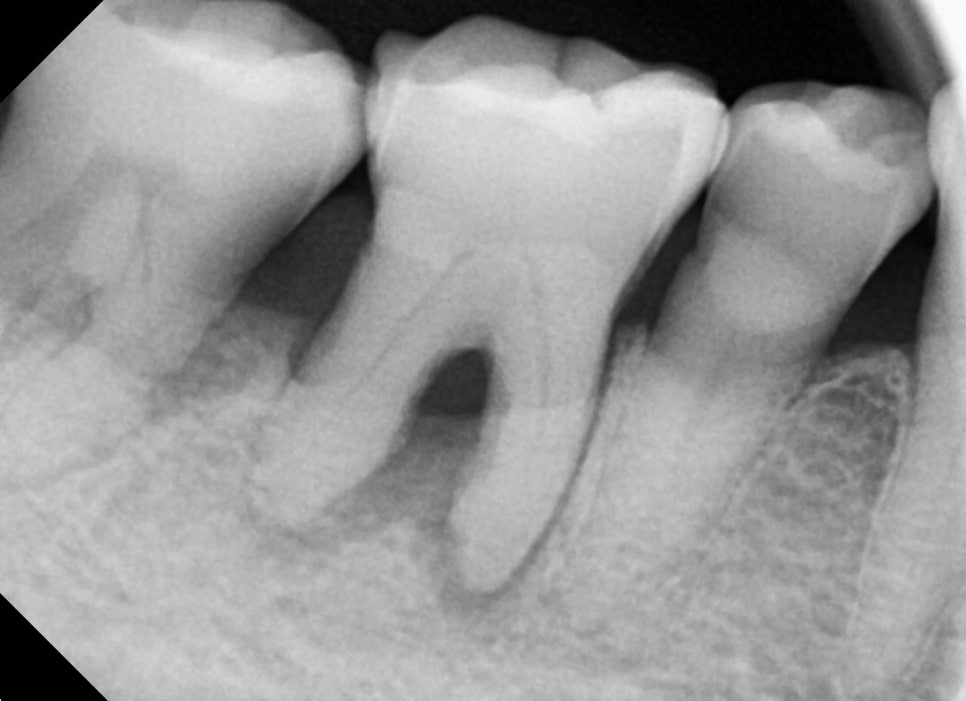

Why Molar Pain Occurs

Molar pain is often caused not only by simple cavities,

but also by gum inflammation or periodontal disease. In one case, a 70-year-old male patient visited the clinic with pain in the lower right

molar, and the examination revealed both periodontitis and

gum inflammation.